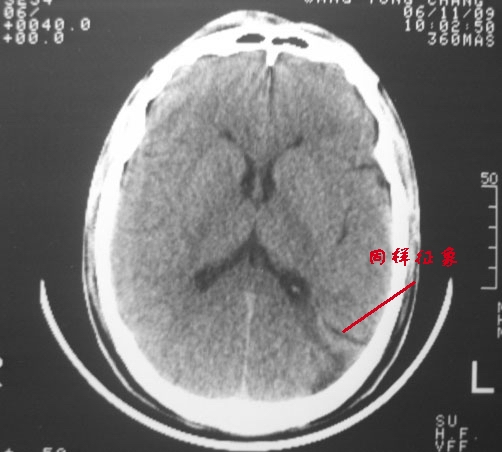

以下是引用dyqct在2006-11-9 15:04:00的发言:[br]左枕叶、双顶叶各见一处似三角形低密度区,边界尚清楚,无占位效应,累及皮质,白质侧未见灰质影。余所见未见异常。[br]考虑:1、脑软化灶;[br] 2、不支持脑裂畸形,该病病变区两侧应有灰质带——即灰质异位,临床上常有顽固性颠痫。当然了脑软化灶也偶会出现颠痫。

以下是引用守望可可西里在2006-11-9 15:06:00的发言:[br][br] 1.左侧枕叶低密度与侧脑室相通,考虑开唇型脑裂畸形。[br] 2.双侧顶叶低密度考虑局部脑沟异常扩大,发育问题。